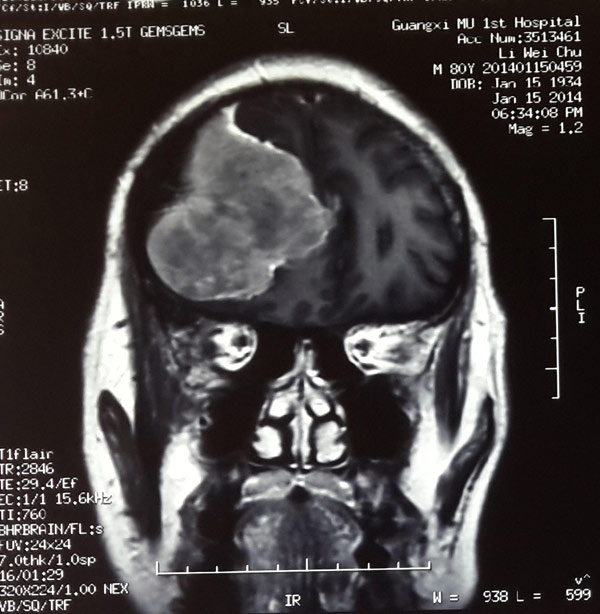

经过确诊,李大爷的病是由右侧额区凸面脑膜瘤引起的。正是这个肿瘤压迫了神经才造成老人左肢无力。但鉴于他年事已高,医生认为手术风险极大,家属在医生推荐下来到瑞康医院神经外科求救。

头颅CT显示,李大爷颅内肿瘤已经长至鸭蛋大小,立即手术是挽救老人生命的唯一办法。

术前可见巨大脑膜瘤